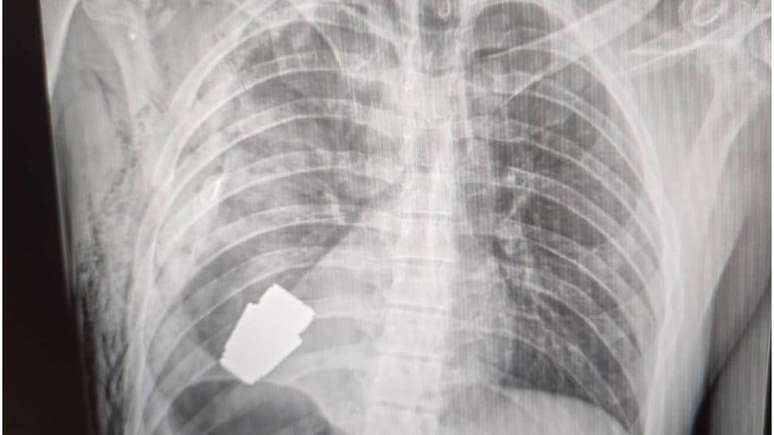

Imagem mostra raio-x da cavidade torácica com granada claramente visível

Foto: Hanna Maliar Facebook / BBC News Brasil